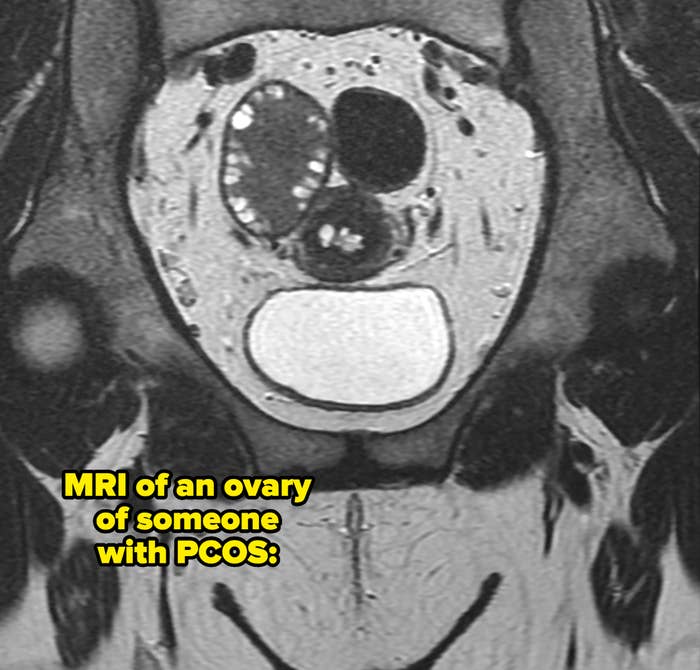

1.“I havePCOSor polycystic ovary syndrome. Growing up, I had really, really heavy periods and super unpredictable cycles, which is a key symptom of PCOS, amongst other things. My understanding was that periods were painful foreveryone,so I just assumed I was being dramatic. It wasn’t until I was diagnosed and started asking my friends about their periods that I realized we were having very different experiences. Like, I was going through two or three times as many pads as they were. Or, like, when they were talking about their periods being late, they meant a couple of days, whereas late for me meant a week or two or no period at all. My uterus, seemingly, does not own a calendar.”